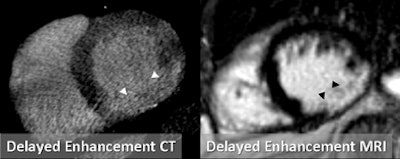

The following paragraphs describe three patients who underwent the comprehensive DSCT protocol along with SPECT myocardial perfusion and MRI for comparison. All images relate to the first patient.

| Images are of a 64-year-old man with a past history of inferolateral myocardial infarction. Rest coronary CT angiography revealed distal right coronary artery occlusion. Functional analysis during systole and diastole showed inferolateral akinesis. First-pass adenosine stress dynamic perfusion CT demonstrated inferior and inferoseptal perfusion defect, confirmed on MRI and SPECT. This perfusion defect corresponds to chronic infarction, as confirmed by delayed-enhancement CT and MRI. Images courtesy of Dr. Gorka Bastarrika, Ph.D. |